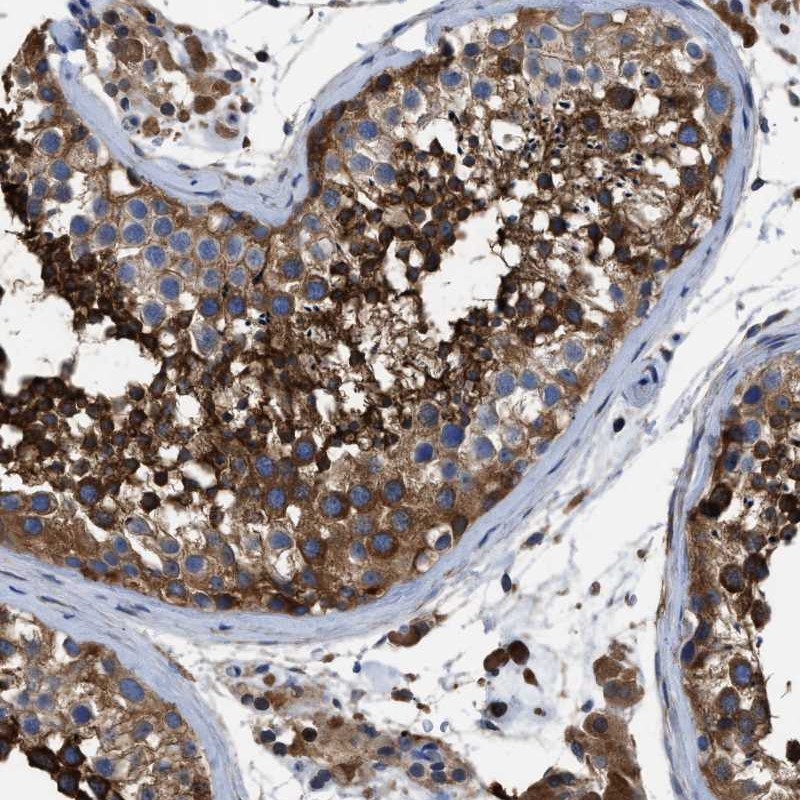

Immunohistochemical staining of human testis shows strong cytoplasmic positivity in cells of seminiferus ducts.